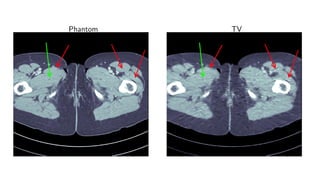

Results for ray transform inversion in 2D.

Compare to:

FBP

Total Variation

Post-processing deep learning by U-Net

Phantom TV

Method PSNR (dB) SSIM Runtime (ms) Parameters

FBP 33.65 0.829 423 1

TV 37.48 0.946 64 371 1

Learned U-Net 41.92 0.941 463 107

Learned Primal-Dual 44.11 0.969 620 2.4 · 105